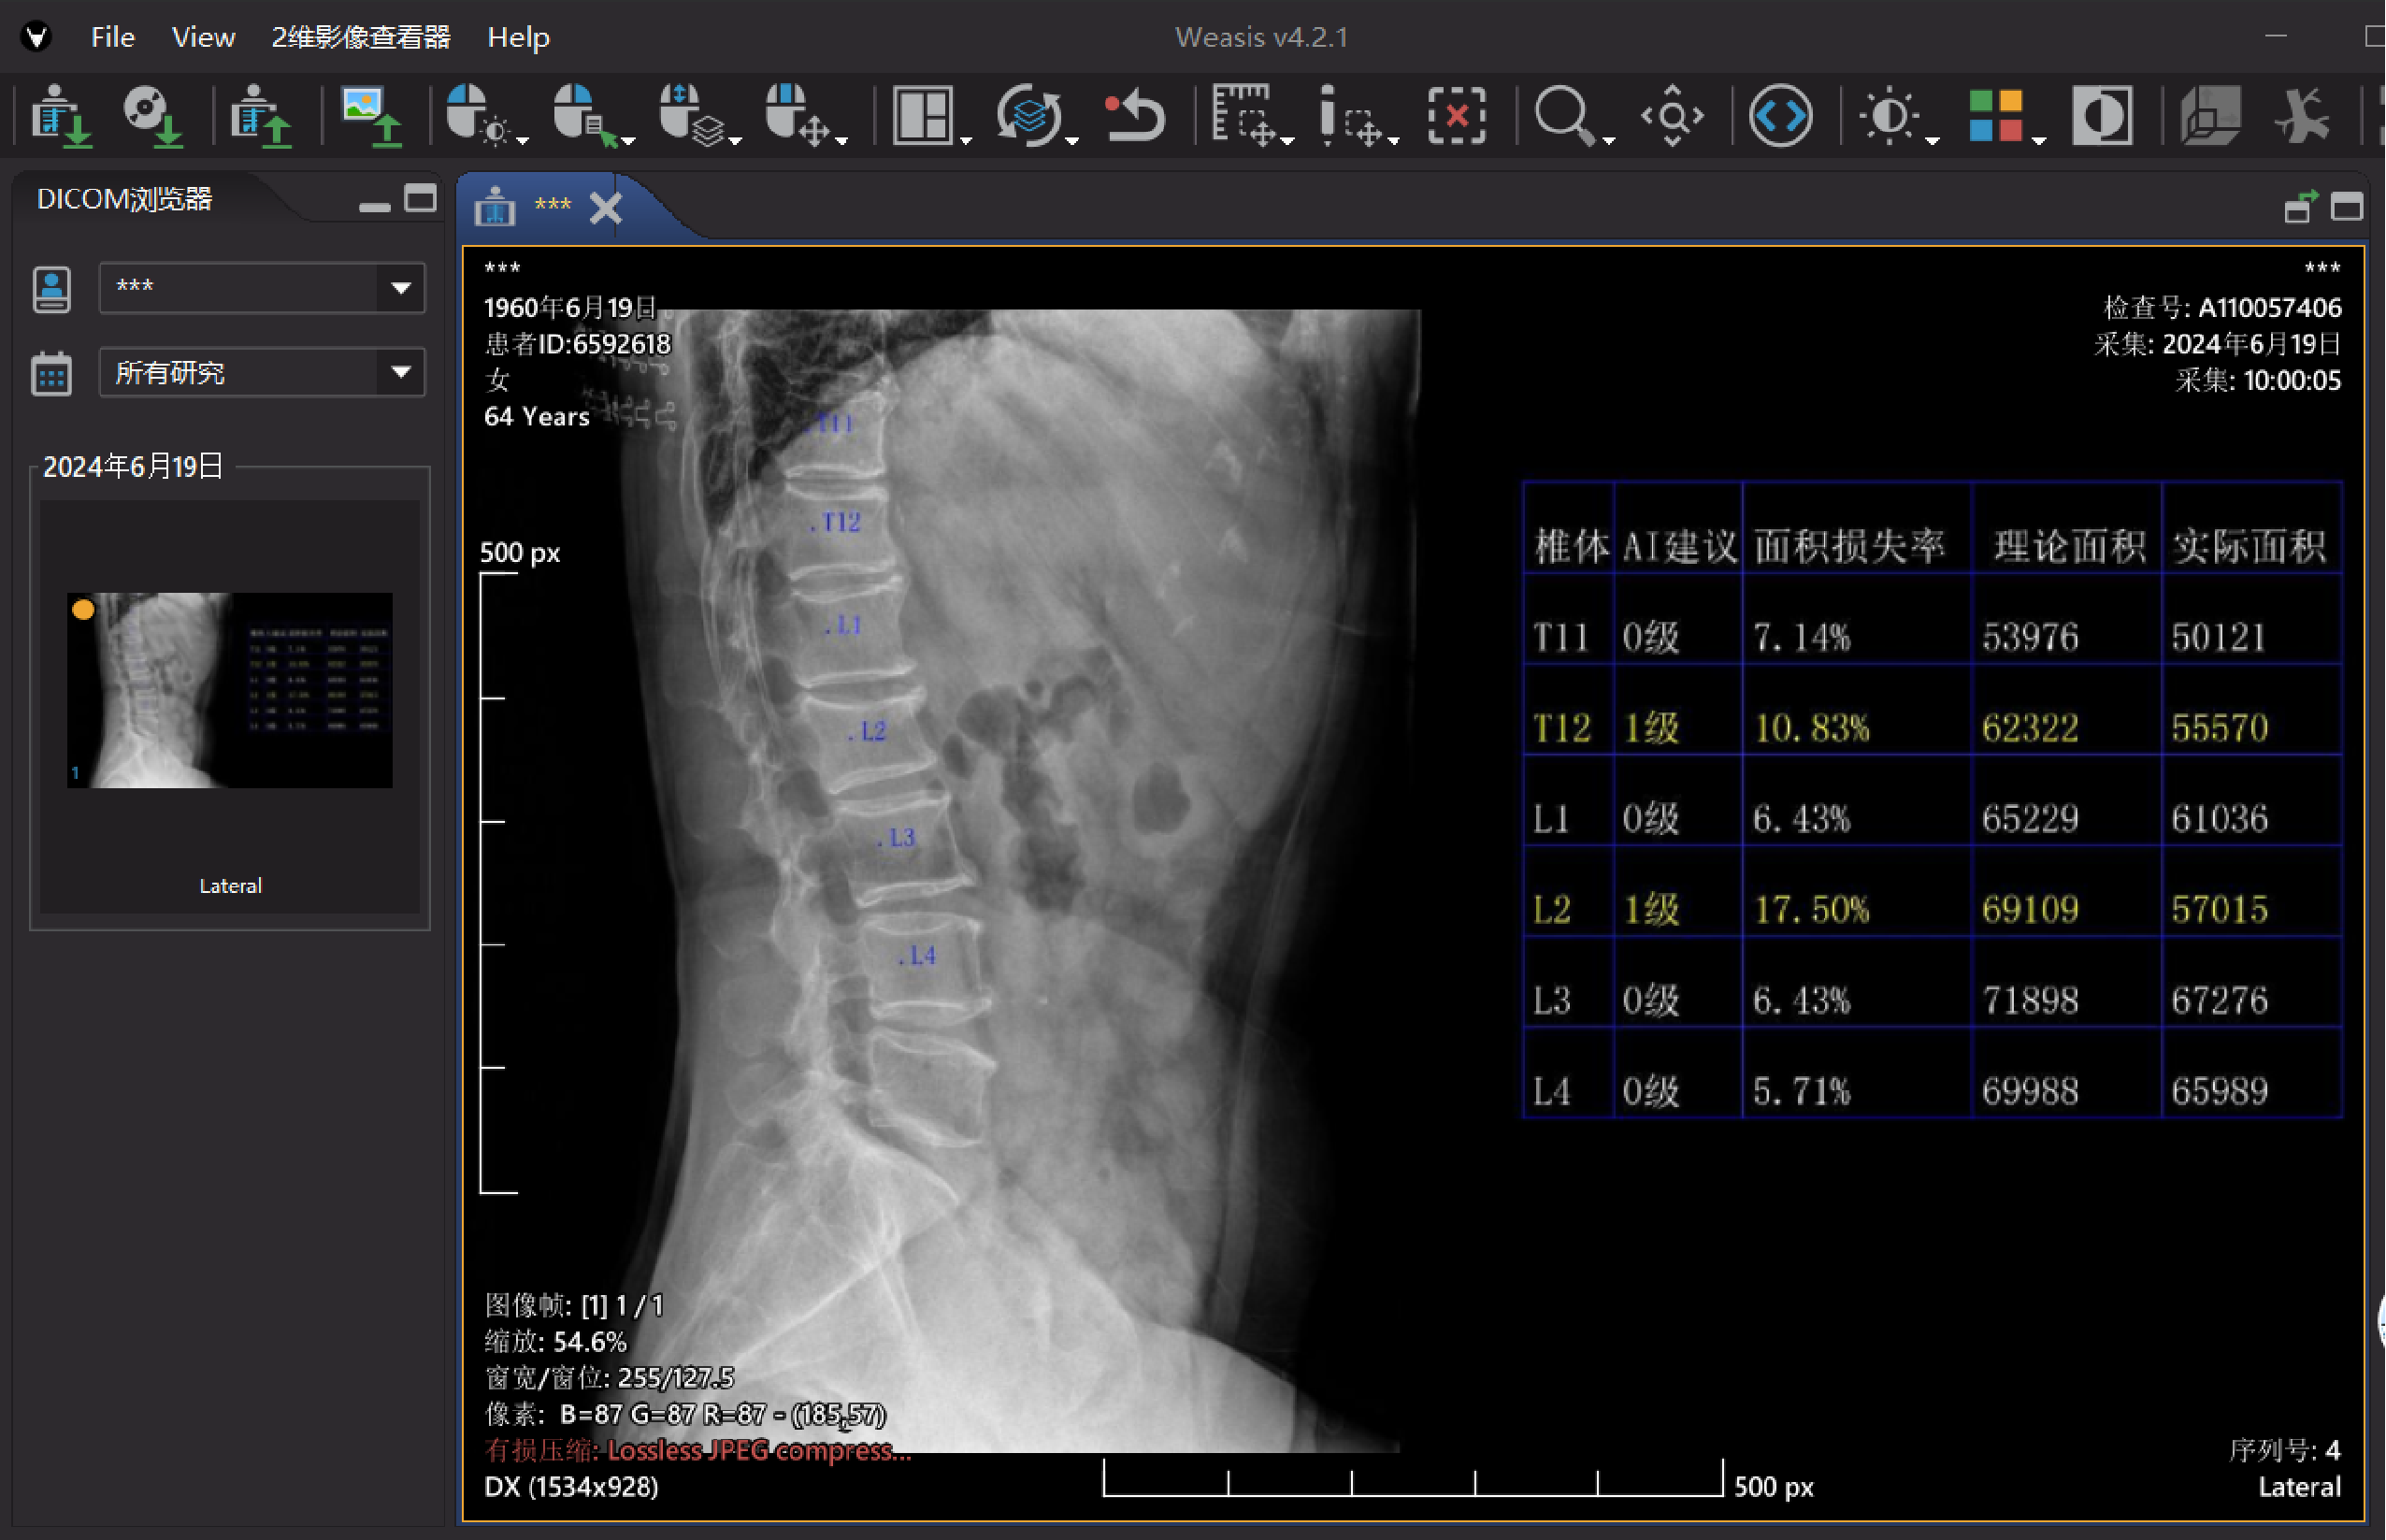

椎体X射线影像处理软件(基于X线片)

全球首个基于X线侧位片的AI影像智能识别系统,通过图像深度学习算法实现椎体自动定位与骨折智能分度识别,显著提升骨质疏松性椎体骨折的影像评估效率和诊断准确性,并已获上海市第二类创新医疗器械认证。